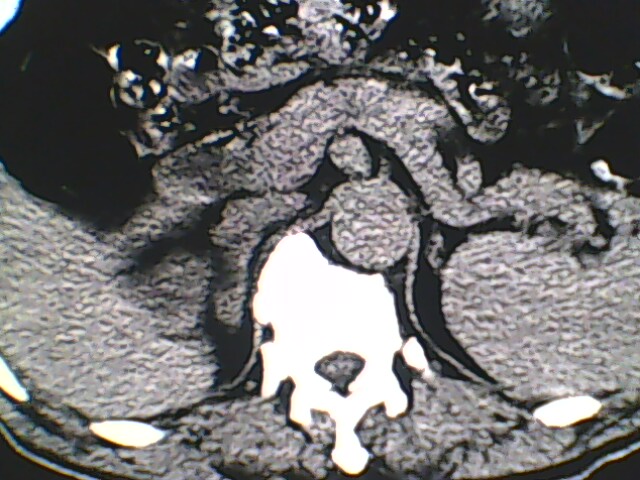

男,56岁,高血压,临床怀疑肾上腺问题,肝脏怎么那么高啊?能描述一下么?

右侧膈膨升,间位结肠,胸腰椎退行性骨关节病,右侧肾上腺可疑增生(图像颗粒太粗,窗太窄,不好看)。

支持 右侧膈膨升,间位结肠;胸腰椎退行性骨关节病;双侧肾上腺可疑增生。

支持右侧膈膨升,间位结肠,胸腰椎退行性骨关节病,右侧肾上腺可疑增生。